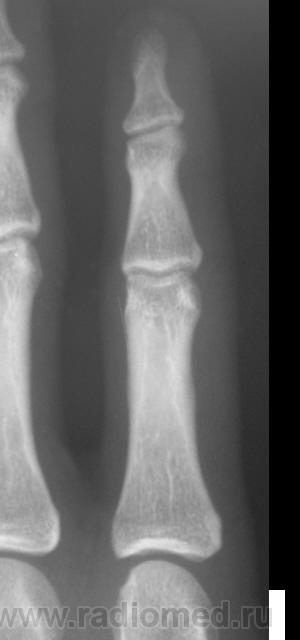

Травма. Пациент направлен на рентгенографию 2 пальца.

Костно-травматических изменений не вижу

Вот это прикол. Настоящая головоломка !!! это инородное тело в области мед края головки осн фаланги 2 пальца.

Ну, не знаю. я тоже ничего не вижу. А тонюсенькая полосочка может быть и артефактом.

Валентин Львович, вы ж укажите, где локальная болезненность. Может перелом основания осн. фаланги?

??? Головка ср.ф. какая-то скошенная, но деструктивн. изм., повреждений не вижу.

Меня тоже смутила форма головки фаланги.